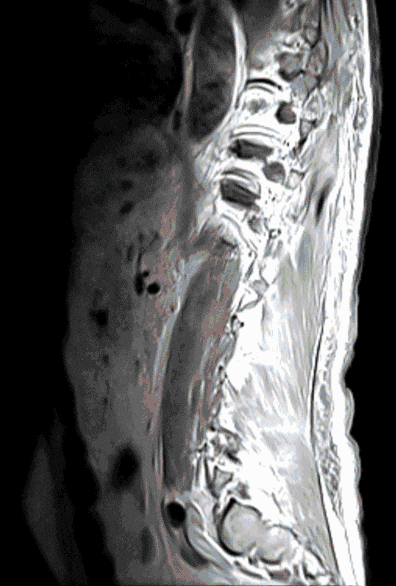

Metastases

Unfortunately, cancer can also spread to the spinal cord. These patients usually have severe neurological deficits and require individualized therapy.